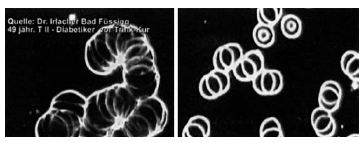

Рис. 17. На левой фотографии видны патологические изменения эритроцитов у 49-летнего больного диабетом 2-го типа (монетное склеивание), на правой фотографии — кровь того же больного через 14 минут после приема католита: эритроциты свободно движутся в кровяном русле. Источник: исследования (архив) доктора Ирлахера.

Иллюстрация к книге — Живая и мертвая вода — совершенное лекарство [i_004.jpg]